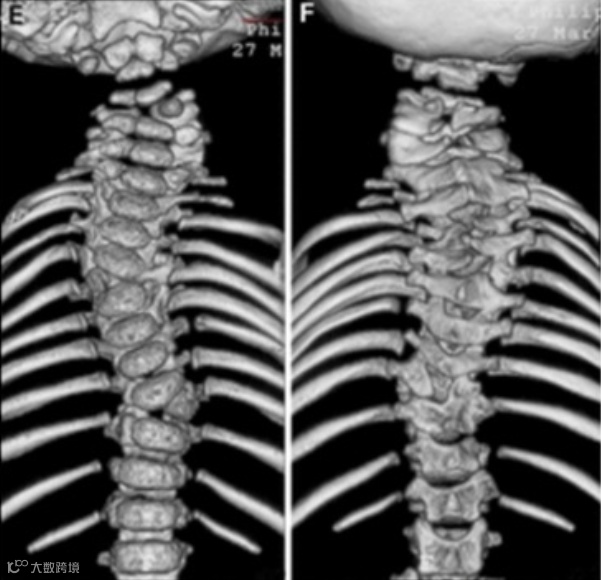

SCDO6型患者多表现为颈椎椎骨缺失或融合等畸形,脖子短,运动受限。椎骨缺损会导致颈椎严重不稳定,在轻微的外部损伤后可能会导致心脏骤停。

SCDO6型:复杂的颅颈交接区畸形,C1-C3的后半部分缺失,C4和T9为左半椎,T4为右半椎